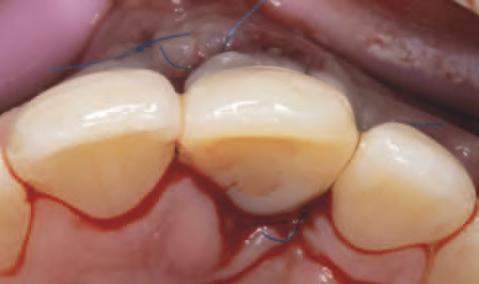

Implantur le subper ostale sunt structur metal ce fabr cate nd vdual pentru a se adapta ș a restab l zonele edentate. Personal zate ș concepute pentru a se potr v morfolog e osoase un ce a pac entulu , mplantur le subper ostale sunt plasate sub per ost ș sunt stab l zate pr n șurubur de f xare care ntră în contact cu osul sub acent ș țesutul f bros care le acoperă. Spre deoseb re de mplantur le convenț onale, mplantur le subper ostale se sprj nă d rect pe os ș prez ntă bontur care emerg pr n țesutur le g ng vale pentru a acomoda proteze f xe sau detașab le totale sau parț ale (un exemplu de implant subperiostal individualizat este ilustrat în fig. 6-14)

Protocolul debutează cu scanarea anatom e osoase a pac entulu folos nd tehnolog a CBCT, ar datele sunt ut l zate pentru o reconstrucț e v rtuală a max larulu edentat. Acestea sunt apo comb nate cu nformaț le d n scanăr le ntraorale ș modelele de ceară d agnost ce pentru a produce un model v rtual 3D cu scopul de a plan f ca corect des gnul mplantulu ș al proteze . Implantur le subper ostale moderne sunt de ob ce fabr cate pr n s nter zarea d rectă a metalulu cu laser (direct metal laser sintering, DMLS), proces în cadrul căru a un laser de

mare putere este ut l zat pentru a top pulber le metal ce strat cu strat. Totodată, se fabr că ș o repl că a mplantulu d n mater al răș n c, astfel încât cl n c anul să poată plan f ca corespunzător ntervenț a ch rurg cală în ceea ce pr vește locaț le structur lor anatom ce v tale ș des gnul adecvat al lamboulu .

În z ua nserăr , după ce s-a real zat o expunere suf c entă a suportur lor anatom ce sub acente, mplantul este ver f cat în pr v nța adaptăr corecte, ar or ce mod f căr necesare sunt efectuate îna nte de plasarea f nală. Implantul este stab l zat pe poz ț e cu șurubur monocort cale nserate pr n găur predef n te în osul sub acent. Lamboul este decolat ș d secat corespunzător pentru a obț ne suf c entă pas v tate care să as gure o înch dere pr n ntenț e prmară în jurul bontur lor expuse ale mplantur lor. După per oada necesară de v ndecare, se au amprentele corespunzătoare pentru fabr carea ș l vrarea proteze f nale.